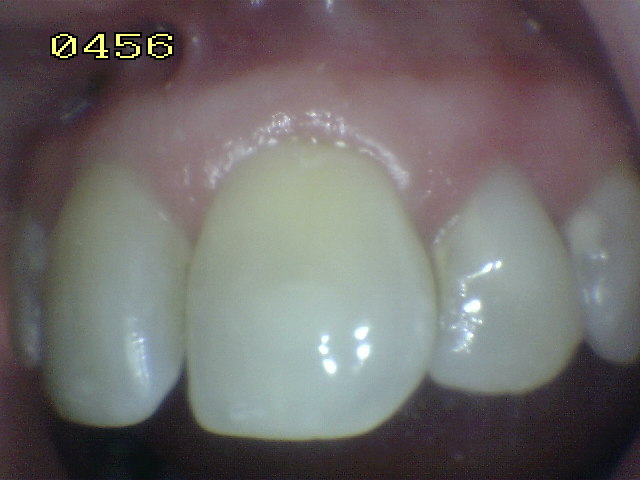

Tratamiento de hipoplasia del esmalte

en 21, semicarilla lumino-activada |

| Caso a tratar |

Aislación absoluta |

Microabrasión con acido

ortofosfórico y pomez |

Caso terminado con

resina de fotocurado A2 |